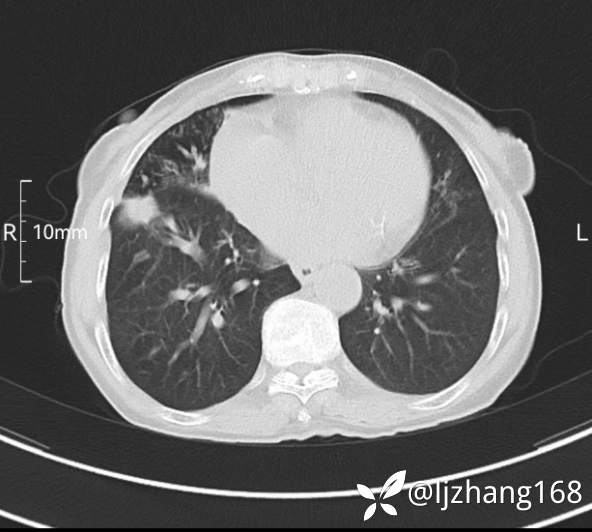

74岁女患,反复咳嗽2月,右肺空洞性病变,炎症OR肿瘤(有病理)

简要病史:2月前开始受凉后出现咳嗽,咳少许白色粘液痰,痰不易咳出,无痰中带血及咯血,无畏寒发热,外院胸部CT提示右下肺空洞病变,脓肿可能性大,常规抗感染治疗效果不佳。既往否认“糖尿病”等病史,有高血压基础病史,无吸烟史。

辅助检查:胸部CT右肺下叶前基底段结节并空洞

临床诊断:右肺空洞:脓肿?